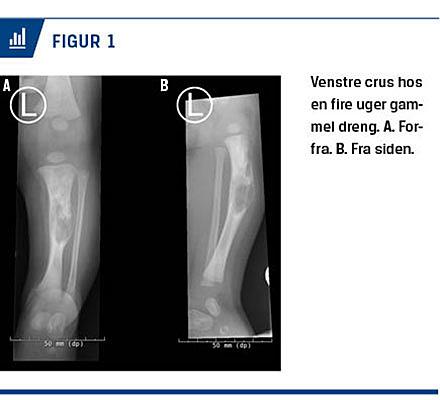

Ved undersøgelsen fandt man drengen i god trivsel. Hofterne bevægedes frit og uømt, og Ortolani- og Barlowtest var negative. På hans venstre underben sås en lille bule, der var øm ved palpation. En ultralydskanning af hofterne viste normale forhold. En røntgenoptagelse af venstre underben viste en tumor, der fyldte det meste af tibia. Tumoren fremstod malignitetssuspekt (Figur 1), og blev foretaget en MR-skanning, hvis resultat fortsat gav mistanke om en mulig malign tumor. Der var en gennemgående fraktur i hele det suspekte område.